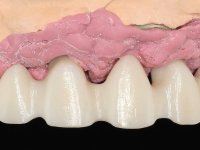

O paciente foi observado conjuntamente e a dúvida que surgiu de imediato foi se seria possível com a regeneração óssea a efectuar poder ser reabilitada naturalmente a zona das papilas interdentárias. Nesse sentido foi feito um enceramento de diagnóstico que contemplaria as duas hipóteses, utilizando ou não a cerâmica gengival. A confecção desse enceramento foi fundamental para expor ao paciente a dificuldade da reabilitação. O wax-up deu origem a um mock-up que foi aprovado pelo paciente e que simultaneamente serviu de guia imagiológica. O caso foi planificado cirurgicamente e realizada uma guia cirúrgica com que foram colocados os implantes. Após 10 semanas foi feita a 1ª impressão para confecção da ponte provisória. Foram criados os primeiros perfis de emergência na gengiva artificial e foi digitalizado o modelo. Por processo de CAD-CAM foi confeccionada uma ponte provisória aparafusada baseada no enceramento de diagnóstico. A ponte trabalhou durante 8 semanas os tecidos moles que foram fielmente copiados numa impressão com técnica de moldeira aberta. Os transferes foram individualizados com resina composta para copiarem fielmente os perfis de emergência criados pela ponte provisória. Confeccionado o modelo de trabalho definitivo, foi realizada uma infra-estrutura em zircónio seguindo a orientação do enceramento de diagnóstico. O assentamento da infra-estrutura foi testado em boca e simultaneamente foi novamente impressionados os tecidos moles com um silicone fluido. Nessa consulta foi feito o levantamento da cor. Os dentes 13 e 23 apresentavam uma saturação anormalmente forte que resolvemos não valorizar, optando por privilegiar a relação com o sector antero-inferior. Foi realizada uma nova gengiva artificial com a impressão que acompanhou a impressão de arrasto com a infra-estrutura. Após a colocação da cerâmica na infra-estrutura foram coladas as meso-estruturas. O trabalho final foi aparafusado lentamente permitindo a adaptação dos tecidos moles.